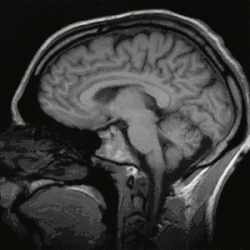

Exame de imagem por ressonância magnética do topo à base do cérebro. O pequeno ponto em cima à esquerda é uma cápsula de vitamina E, que serve de orientação na compilação das imagens.

Nesta imagem encontra-se um cérebro a ser auscultado por ressonância magnética.